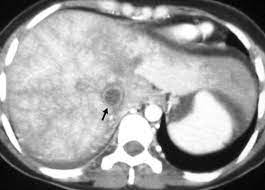

Chiasmata -mə-tə or chiasmas also chiasms 1. Esophageal varices are extremely dilated sub-mucosal veins in the lower third of the esophagus. Located in metro Denver northern Colorado and western Nebraska serving all of the Front Range our team consists of board-certified and fellowship-trained interventional radiologists. This results in hepatic congestion similar to Budd-Chiari syndrome and post-sinusoidal portal hypertension. The patients condition should be monitored throughout the procedure. They are most often a consequence of portal hypertension commonly due to cirrhosis. Toxic injury to liver sinusoids causes sloughing of endothelial cells that embolize to hepatic venules and cause eventual fibrosis of the venules. Coin in the Esophagus. There is no clear consensus regarding the number of occluded veins some authors claim that there should be at least one occluded hepatic vein 7 others state that there are no significant.

Carcinoma of the Colon. Budd-Chiari syndrome a blockage in one or more veins that carry blood from the liver back to the heart. And coumarin skin necrosis adrenal gland hemorrhage and infarction. Toxic injury to liver sinusoids causes sloughing of endothelial cells that embolize to hepatic venules and cause eventual fibrosis of the venules. Chiari malformation CM is a structural defect in the cerebellum characterized by a downward displacement of one or both cerebellar tonsils through the foramen magnum the opening at the base of the skull. Embolism and thrombosis of. La présence dune ou plusieurs affections prothrombotiques est fréquente La prise en charge repose sur un traitement anticoagulant précoce le traitement de l.